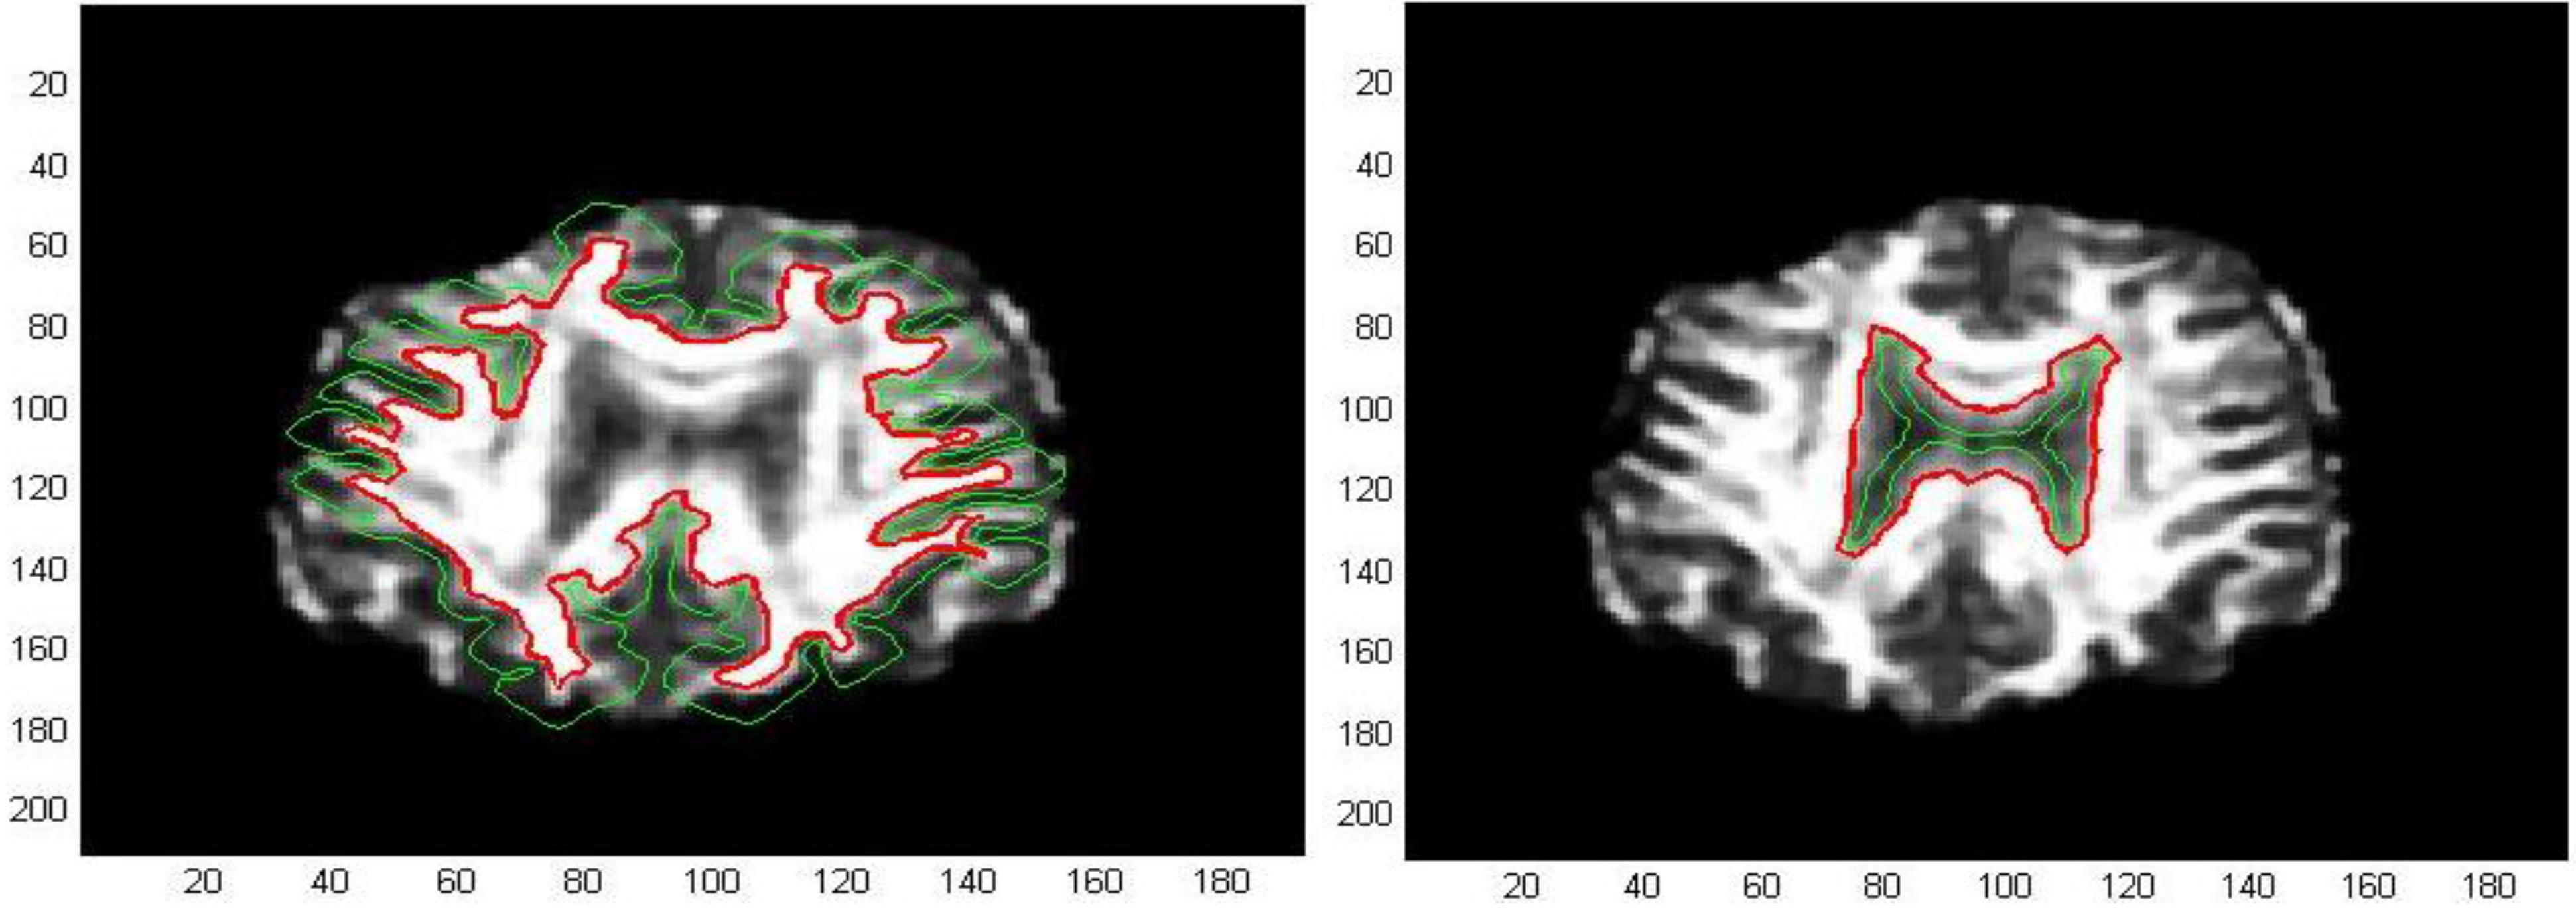

The first processed GM image (Figure 11) refers to a subject of the control group (see the first image of Figure 12). The force field has been evaluated from Equation (9) after eight iterations, the overlapping green curves represent initial contours that are automatically selected from the contour map of divergence. In Figure 13 and Figure 14 we have treated GM images derived from two patients affected by Alzheimer’s disease and they refer respectively to the second and third images which are shown in Figure 12. Once edges are detected, we produce a boundary representation of gray matter that can be used for an automatic analysis of shapes from the geometrical, metrical or morphological point of view.

Figure 11. Edge extraction with AVF force field after 8 iterations.

Algorithms 05 00636 g011